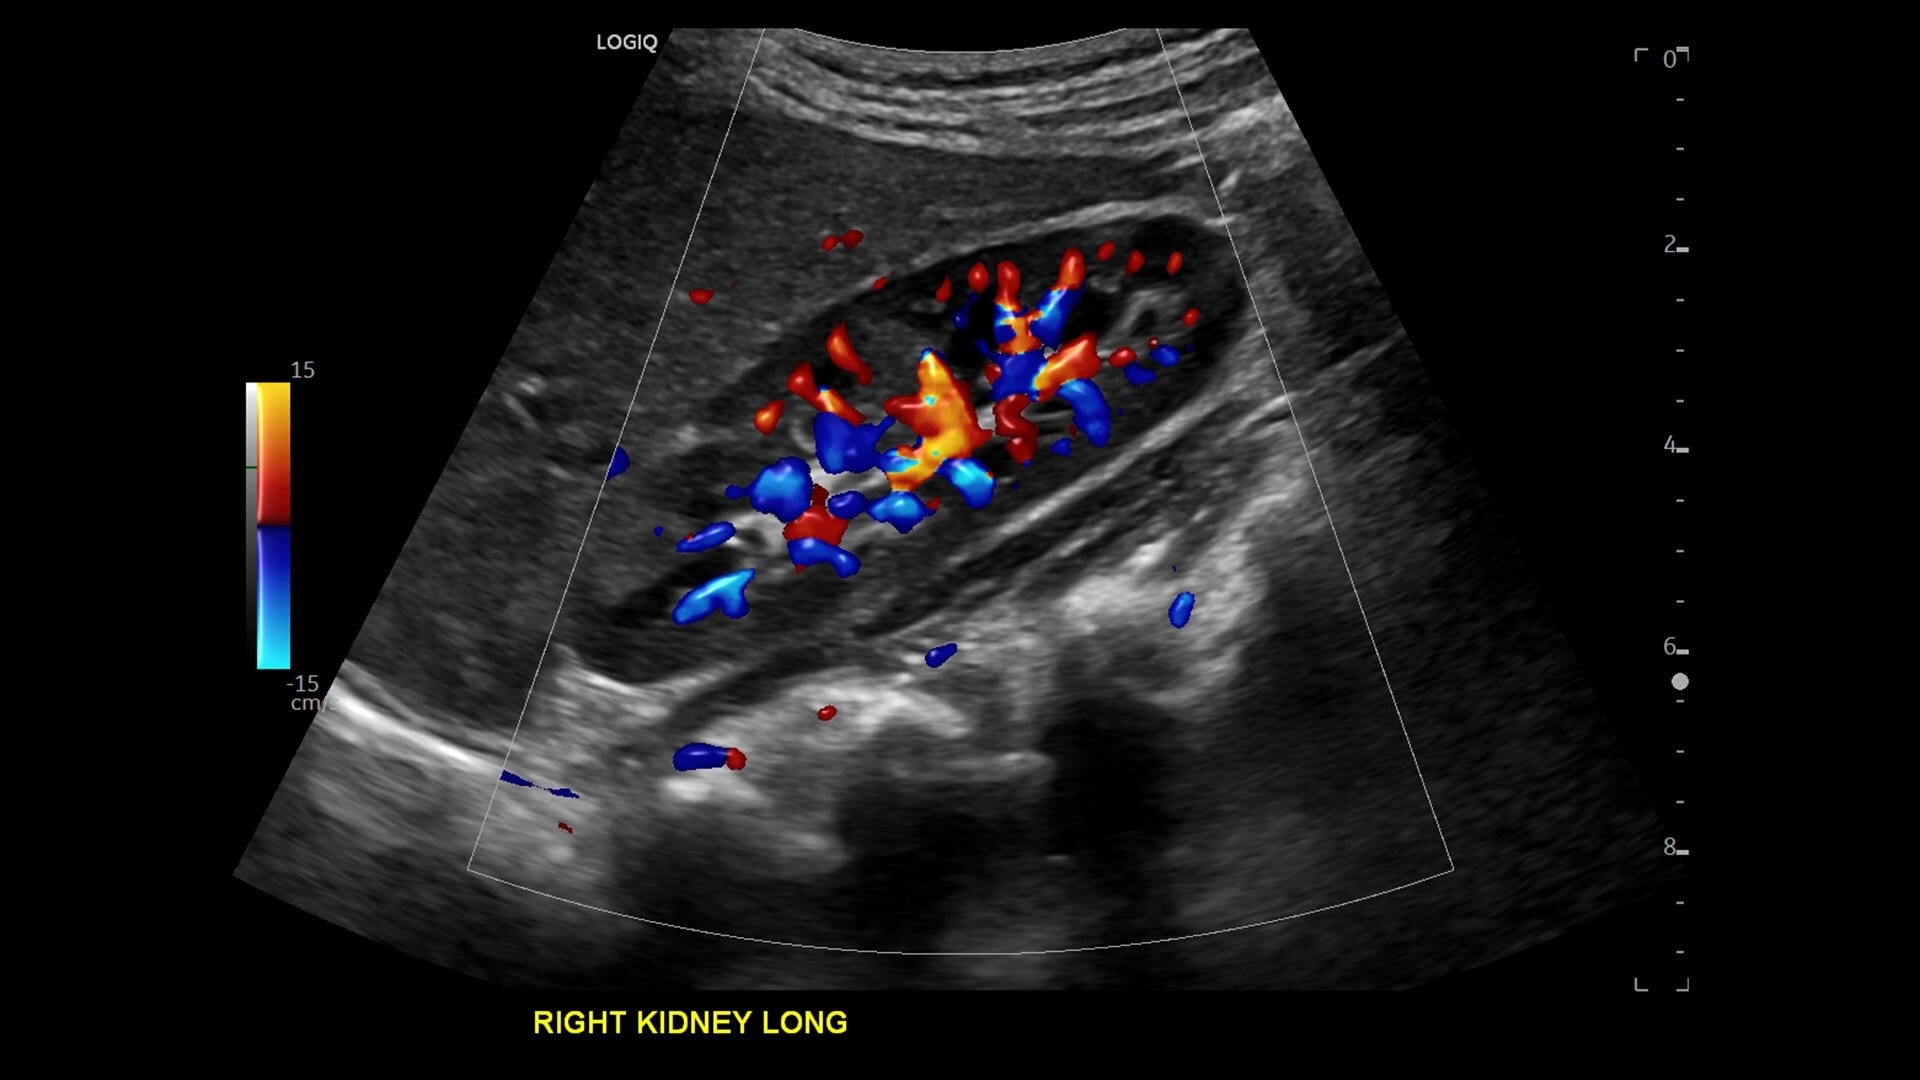

• Advanced flow modes give you the flexibility, from large vessels to fine microvascular detail, to visualize blood flow with precision

• New Auto Renal Measure Assistant: Automatically detects kidney and measures length, height and width in seconds*